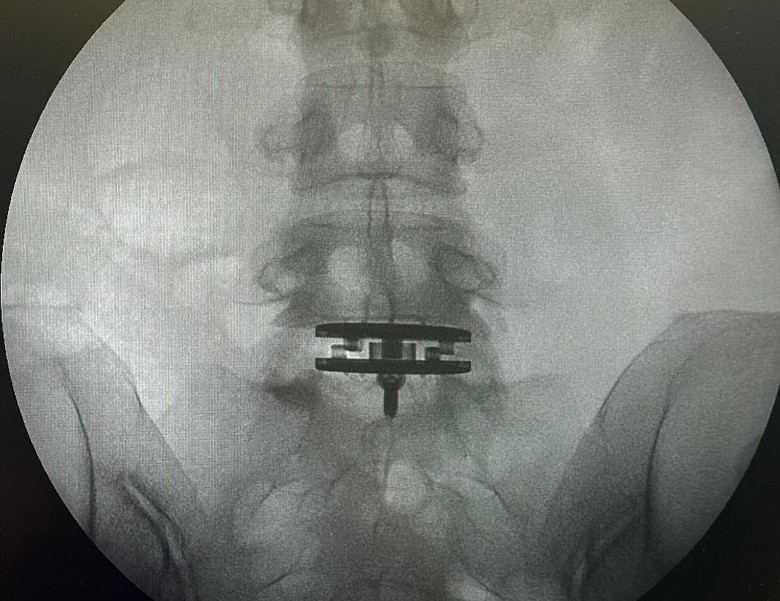

徐濠萦昨日在IG PO出她在手术室与医护人员合照,估计是进行腰部手术前拍摄,照片中更可见到她神情轻松。同时也附上数张X光片,可以见到片中腰椎接近盆骨的位置有东西矫正脊椎,她用英文写下:“由于腰椎间盘突出问题,我多年来一直忍受背痛。2022年曾接受手术,但我的腰痛仍然存在。”随后她PO出在手术室与医护人员合照,估计是进行腰部手术前拍摄,照片中更可见到她神情轻松。

热爱运动的她因椎间盘突出,逼不得已停止重量训练,她表示这种情况严重影响了日常生活,“每当我打喷嚏时都会感到剧烈疼痛”,医生因此建议进行椎间盘置换手术。她感叹:“这次手术很可能是我人生中除了20年前诞下女儿后,最重要的一次手术。”她上载的照片中有一张可以见到是“加油妈妈!”相信是来自宝贝女儿陈康堤的鼓励及祝福。